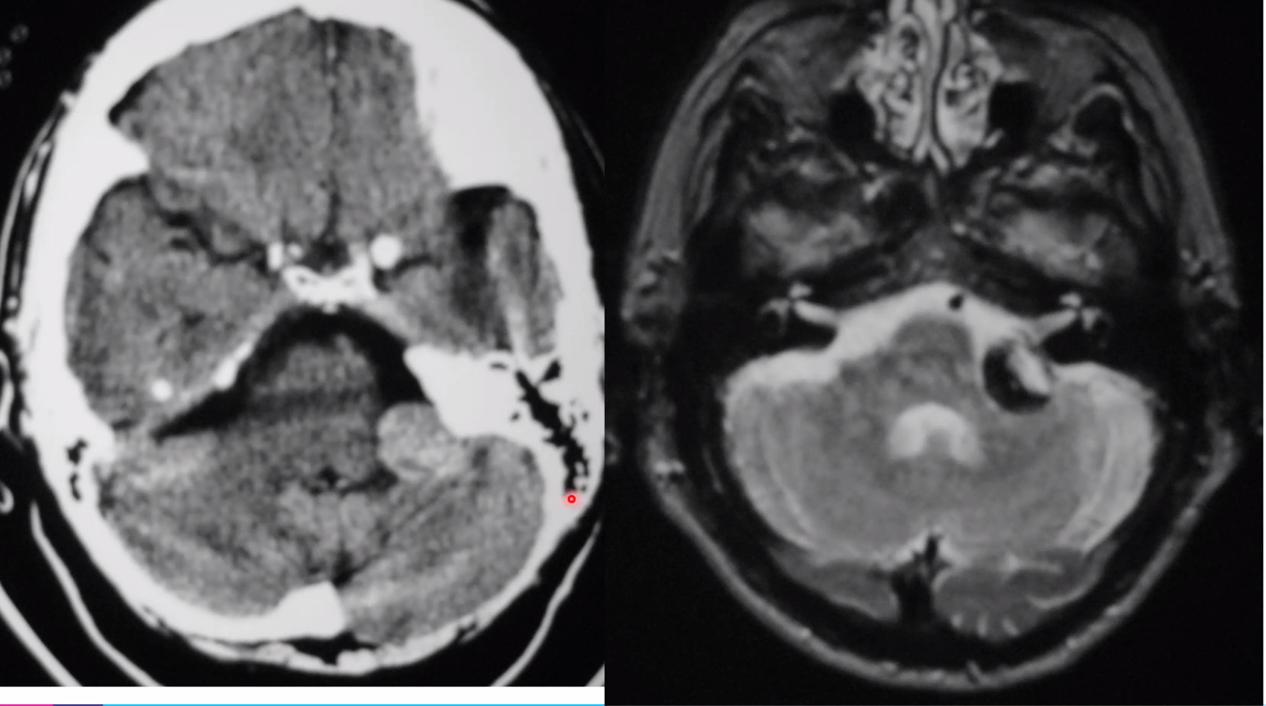

vein of galen malformation

left AICA aneurysm

key is the CTA of the head –> think they are showing an aneurysm

superior sagittal sinus thrombosis